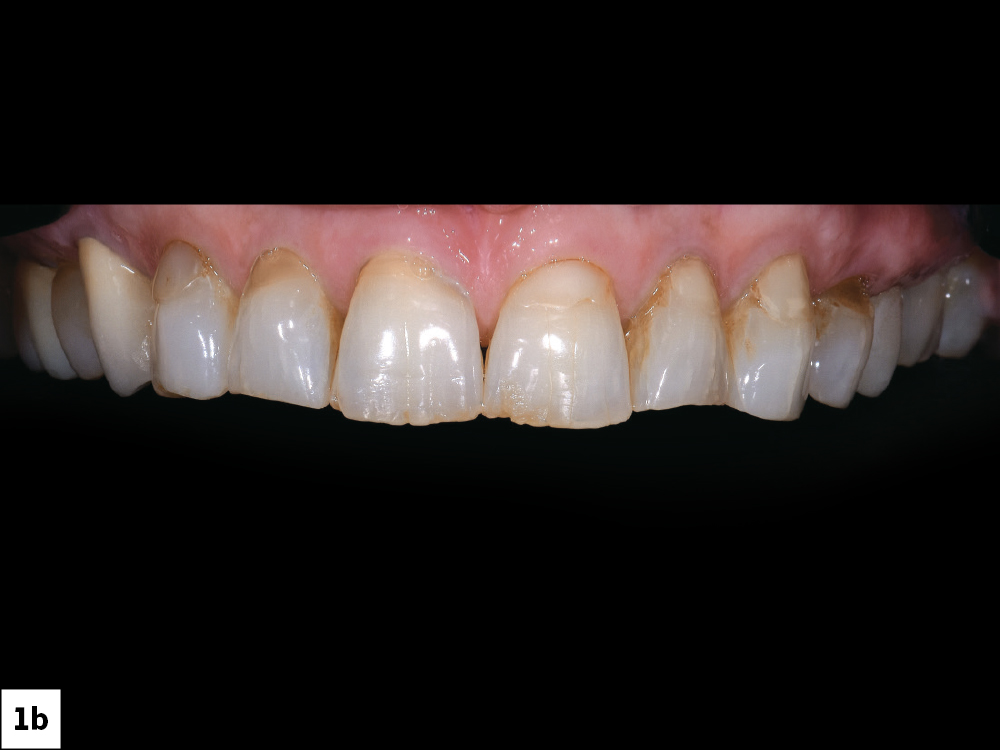

The patient presented with failing Class V restorations, cervical wear, discoloration and chipping of the incisal edges

Figures 1a, 1b: The patient presented with failing Class V restorations, cervical wear, discoloration and chipping of the incisal edges.